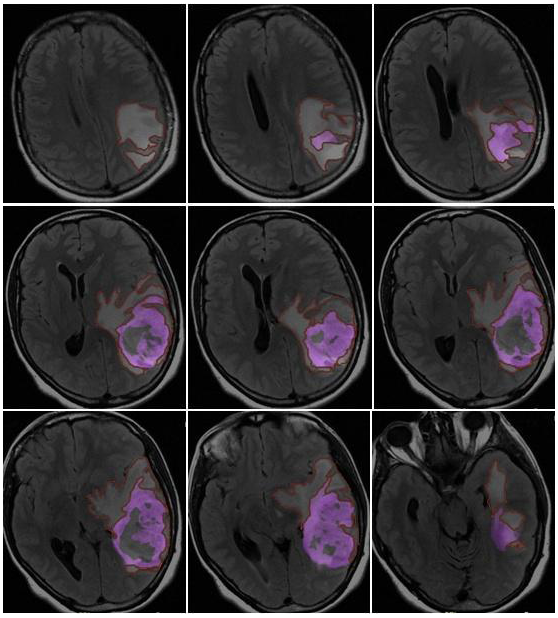

- Morphological appearance: We divided GB lesions into three categories based on the enhancing wall thickness: thin, <3 mm; thin-nodular, when the enhancing wall showed focal thickenings > 3 mm; and nodular, when solid appearance was predominant and intratumoral necrosis was absent or <1.5 cm3. A total of 11 (13%) masses showed a thin pattern, 51 (58%) showed a thin-nodular pattern, and 25 (29%) showed a nodular pattern.